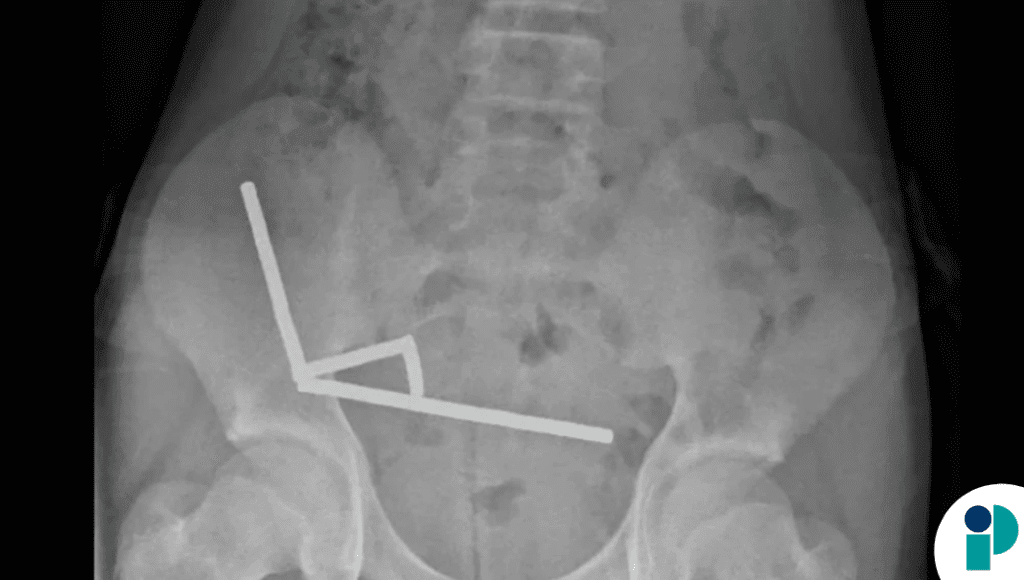

Un niño de 13 años en Nueva Zelanda tuvo que ser sometido a una cirugía mayor después de ingerir entre 80 y 100 imanes de alta potencia. Los pequeños imanes de neodimio, de apenas 5×2 milímetros, se habían adherido entre sí dentro del intestino del menor, formando cuatro cadenas que provocaron daños severos en el tejido.

Durante la cirugía, los especialistas extrajeron los imanes y debieron retirar partes de intestino comprometidas por la presión magnética.